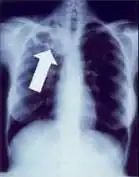

-

Dense homogenous opacity in right, middle and lower lobe of primary pulmonary TB. -

Chest x-ray showing dense opacity pleural effusion in the lower left lung of primary pulmonary TB.